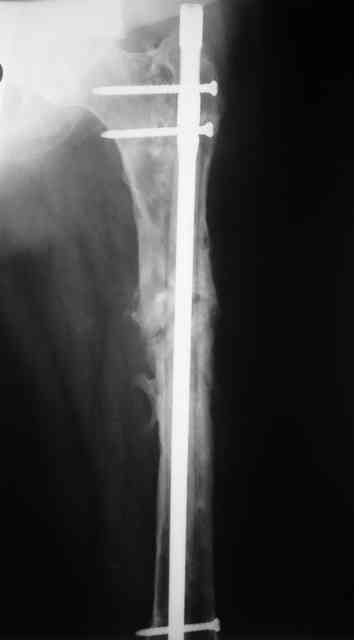

Вчера наш пациент был на контрольном осмотре. Вроде все идет нормально. Рентгенограммы от 25 сентября 2007 г. (прошло 5 месяцев после операции) прилагаю.

В качестве демонстрации лечения канального остеомиелита бедренной кости представляем пациентку (см. parts 2 и 3), которая как раз сегодня была у нас на контрольном осмотре. В мае этого года мы произвели ей фиксацию бедренной кости штифтом-спейсером по поводу ложного сустава и канального остеомиелита бедренной кости. Через 4 недели после операции свищи закрылись. Сейчас она ходит с полной нагрузкой на конечность.

Иллюстрации:

4, 5, 6 - рентгенограммы бедра и фотографии пациентки (прошу прощения за низкое качество рентгеновских снимков) от 7 сентября 2007 г.